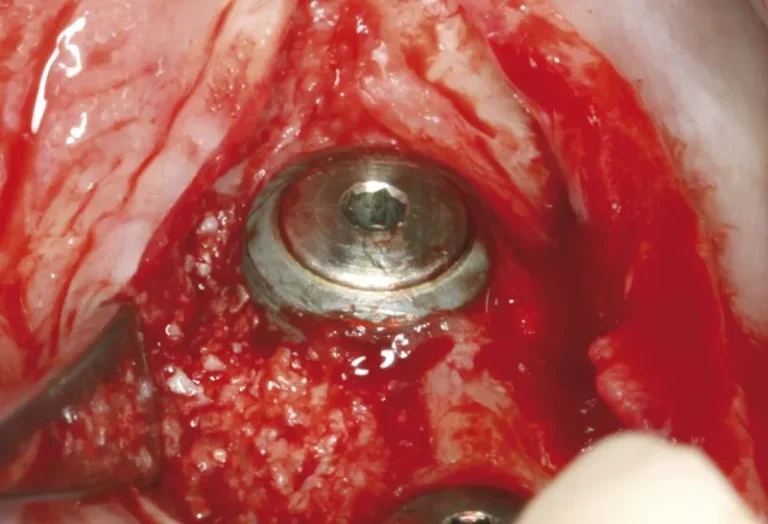

La regeneración ósea es un procedimiento quirúrgico fundamental en implantología dental que permite recuperar el volumen y la densidad del hueso maxilar o mandibular cuando este se ha perdido. Este tratamiento se vuelve necesario cuando el paciente no dispone de suficiente tejido óseo para sostener un implante dental de manera segura y estable. Mediante el…

La osteointegración es el proceso biológico fundamental que determina el éxito de los implantes dentales. Durante este fenómeno, el hueso del maxilar crece y se fusiona directamente con la superficie del implante de titanio, creando una conexión estructural y funcional que garantiza la estabilidad a largo plazo. Este proceso, descubierto por el profesor Per-Ingvar Brånemark…

La sanación de un implante dental es un proceso gradual que varía según cada paciente. Generalmente, la integración completa del implante con el hueso (osteointegración) tarda entre 3 y 6 meses, aunque la recuperación inicial de los tejidos blandos ocurre en las primeras semanas. Durante este período, es fundamental seguir las indicaciones del especialista para…